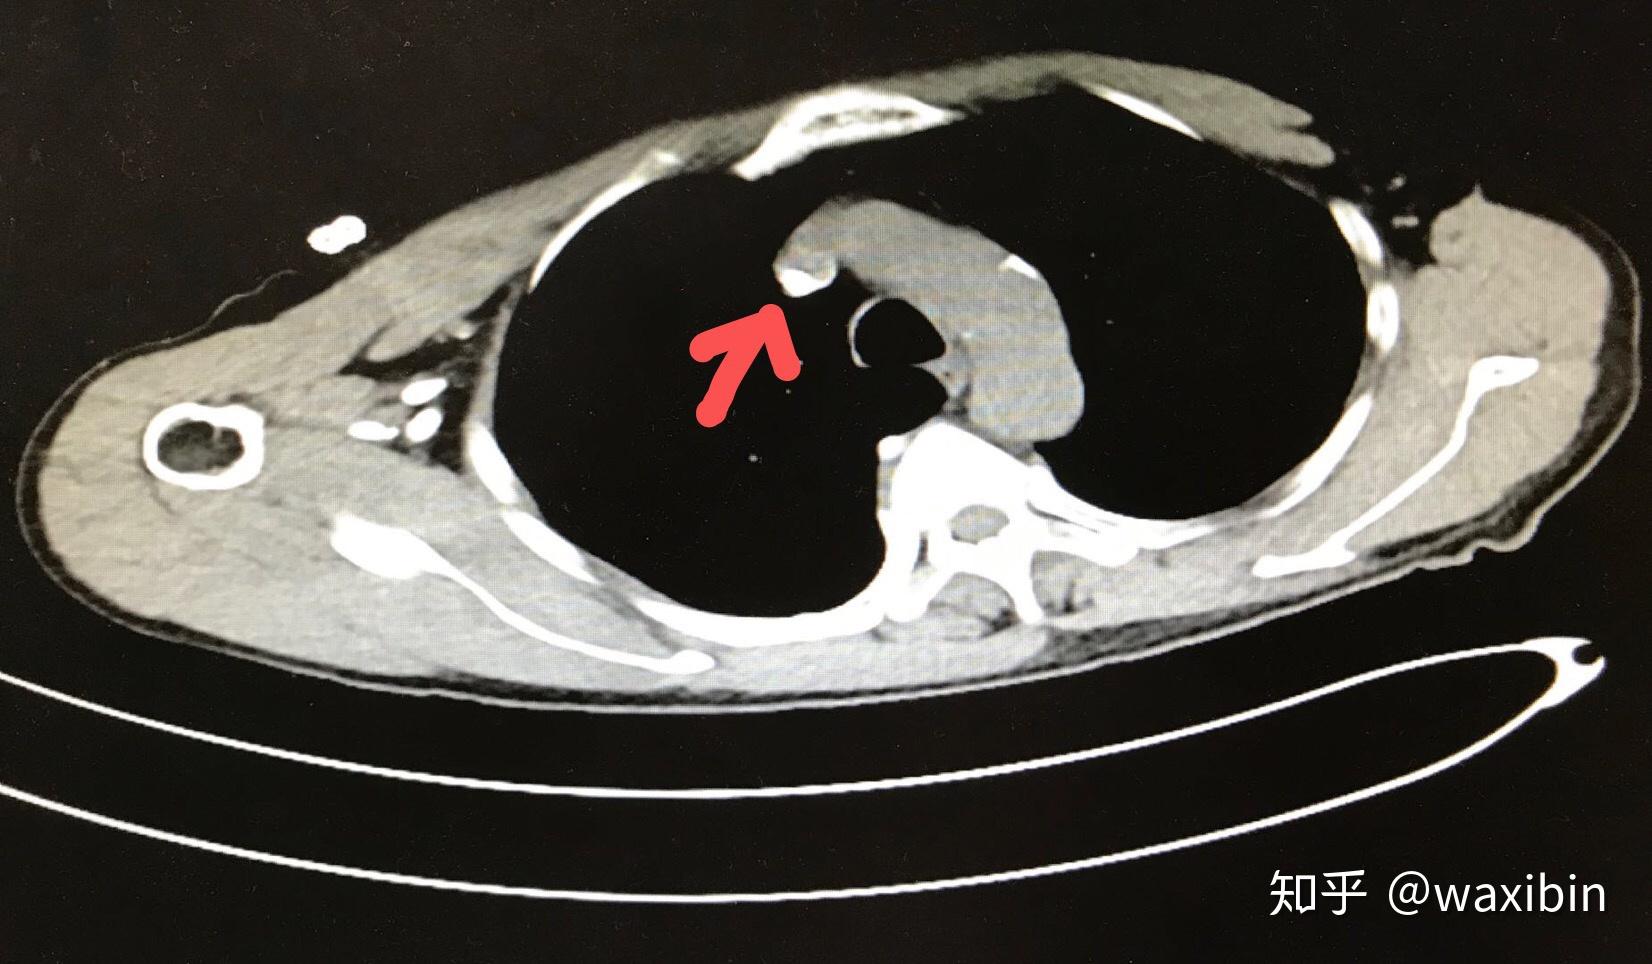

上纵隔轴位平扫ct显示无左头臂静脉,相反可见左(白箭头)右(白箭)上腔